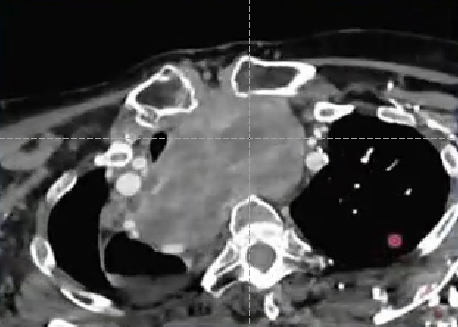

Thyroid artery embolization for Goiter reduction,TAEGR 甲状腺肿大减容动脉栓塞

甲状腺肿大

病因:不是癌症,但5%会含有甲状腺癌(PMID 31542786)